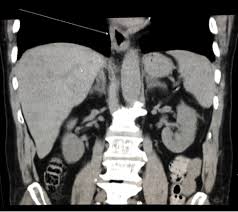

Esophagitis Concise Medical Knowledge

Esophagitis Concise Medical Knowledge from cdn.lecturio.com

Esophagitis refers to inflammation of the esophagus. B from levine ms, woldenberg r, herlinger h, et al. Cobblestone esophagitis (эзофагит со слизистой булыжной мостовой). Behr j, kreuter m, hoeper mm, wirtz h, klotsche j, koschel d, andreas s, claussen m, grohé c, wilkens h, randerath w, skowasch d, meyer fj, kirschner j. Eosinophilic esophagitis attributed to gastroesophageal re. Canalejo castrillero e, garcía durán f, cabello n, garcía martínez j. Esophagitis may cause odynophagia and even esophageal hemorrhage, which is usually occult but can be massive. Healing and relapse of severe peptic esophagitis after treatment with omeprazole.